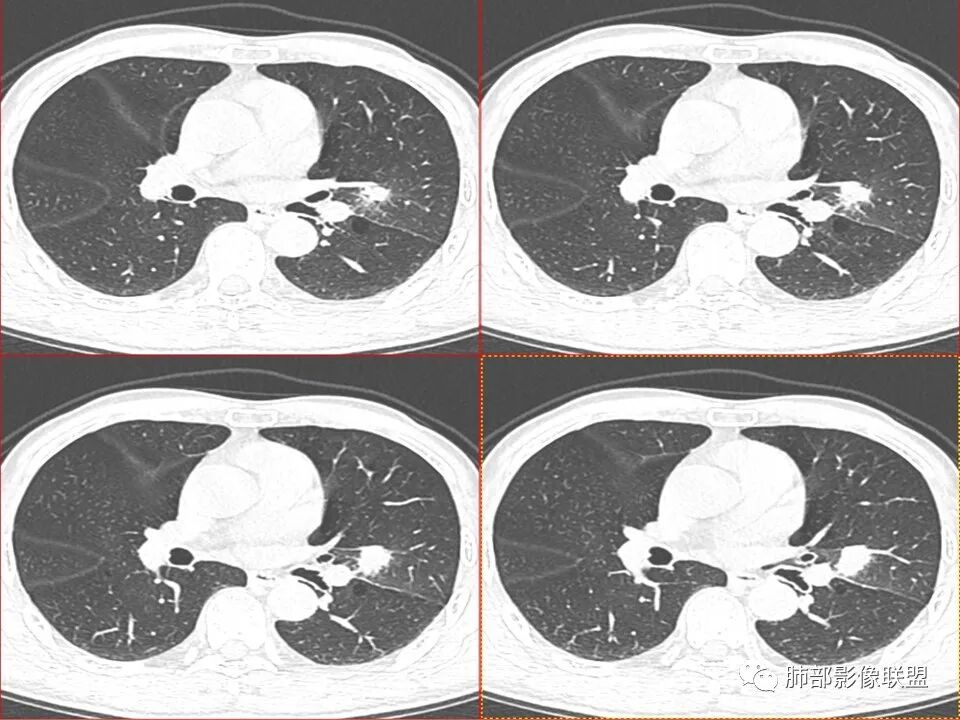

左肺上叶舌段近肺门区不规则结节,密度较均匀,结节边缘平直为主,可见粗短毛刺、毛刺偏软,浅分叶,收缩力不强,膨隆也不明显,周围可见模糊GGO,病灶内部支气管显示不清,病变远端支气管明显扩张,病灶与叶间裂呈宽基底相连,见刀切征,并见叶间裂多发结节影,叶间裂未见明显移位。

患者推测中老年人,无明显临床症状,肺气肿背景不明显,虽然病灶整体炎性征象较多,叶间胸膜多发结节,常规要考虑结核和腺癌,PET-CT肿瘤和炎性病变都可以高摄取,敏感性高,但特异性不高,而且腺癌周围缺乏清晰的磨玻璃及收缩力不强,故暂不考虑;虽然左肺上叶舌段病灶与支气管关系密切,如果周围磨玻璃推测为早期的阻塞性炎症,还有CYFR轻度升高,鳞癌不能除外,但是病灶的整体形态比较符合炎性改变。本病例可惜未行CT增强扫描,无法观察结节的强化特点及病灶内血管走行情况。